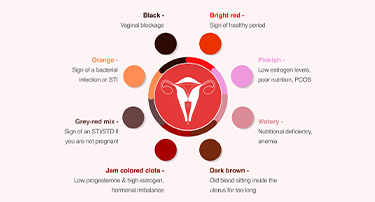

What Your Period Blood Color Says About Your Health?

Periods are a natural part of a woman’s life, but did you know the color of your period blood can provide insights into your health? From pink to black, the shade and consistency of menstrual blood can indicate hormonal changes, underlying medical conditions, or even your overall well-being. Understanding what your period blood color means is essential for maintaining reproductive and general health.